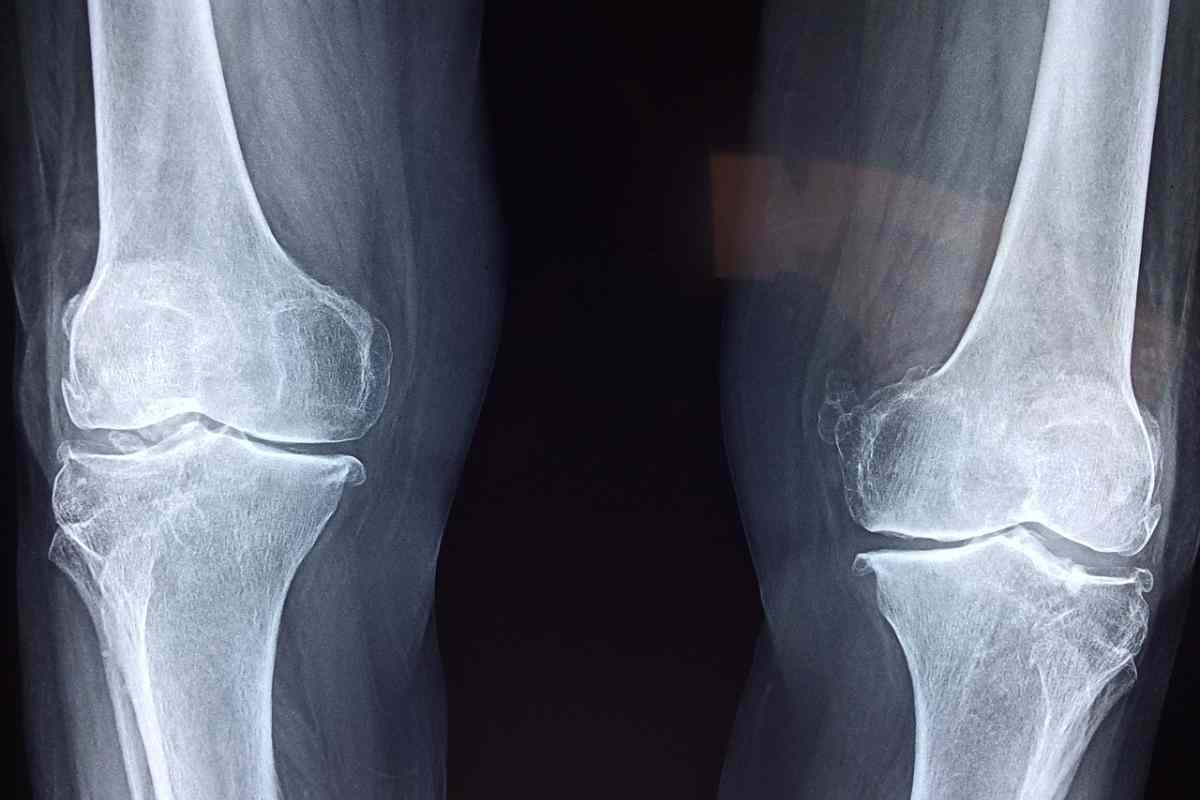

Lastra ginocchio

Infortunio terribile, il verdetto è pesantissimo: lesione del crociato (Pixabay) – Sportitalia.it